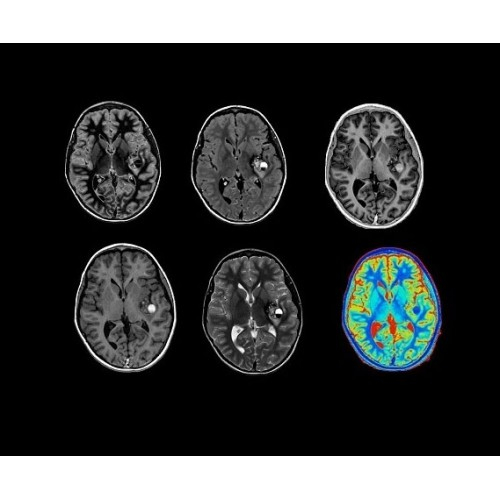

Стандартный пакет приложений SIGNA Works позволит вам достичь желаемых результатов в клинической практике благодаря набору высокоэффективных средств визуализации. Программные приложения, входящие в состав данных клинических пакетов, включают широкий спектр контрастов, функции обработки 2D- и 3D-данных, а также возможность коррекции артефактов движения. SIGNA Works предоставляет набор инструментов, необходимых для проведения эффективного клинического исследования.

• HyperWorks — пакет програмных приложений, который включает технологию HyperSense для поразительной визуализации и скорости.

• ImageWorks — повысит производительность МРТ благодаря визуализации высокого качества с MAGIC, четкими результатами пост-процессинга с READYView.

Технология полной оцифровки изображения Total Digital Imaging (TDI) предлагает потрясающие достижения в области визуализации:

• Технология Direct Digital Interface (DDI)использует независимый аналого-цифровой преобразователь для оцифровки сигнала от каждого из 128 радиочастотных каналов, что обеспечивает значительное увеличение качества за счет уменьшения фонового шума.

• Технология Digital Micro Switching (DMS)— это следующее поколение технологий радиочастотных катушек, основанное на замене аналоговых схем блокировки сверхбыстрыми микропереключателями (MEMS).

• Digital Surround Technology (DST)— это новая технология объемной оцифровки данных, которая объединяет сигналы от каждого элемента катушки. Прекрасное соотношение сигнал/шум и чувствительность поверхностных катушек в сочетании с превосходной однородностью и высокой проникающей способностью встроенной радиочастотной катушки — все это позволяет создавать качественные изображения не только позвоночника, но и всего тела.